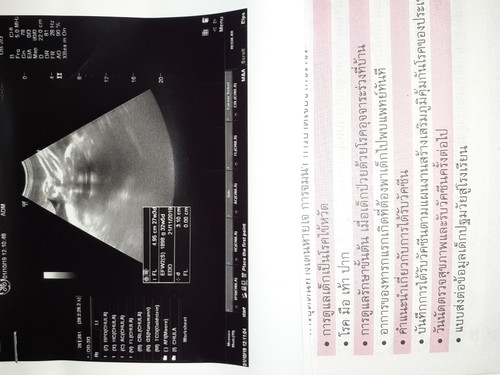

น้ำลูก1,800ในใบซาวบอกว่าอายุครรภ์32+5ตามจริงตอนนี้36+2แล้วเราควรเชื่ออะไรดีงงมากไปซาวมาวันนี้หมอบอกน้องตัวเล็กเกิน

เด็กตัวเล็กมากนะแม่ ต่ำกว่าเกณฑ์อย่างที่หมอพูดค่ะ ต่ำกว่าเกณฑ์เยอะเลยนะแม่เกือบ4วีคเนะ ดูตารางด้านล่างนะคะแม่ ถ้า36วีคน้องควรมีน้ำหนักตัวอยู่ที่2,600แล้วค่ะ ใกล้จะคลอดแล้วบางบ้าน37วีคก็คลอดแล้วค่ะ อัลตราซาวด์จะคำนวณจากขนาดตัวเด็ก แม่บำรุงเยอะๆค่ะ กล้วยน้ำว้า ไข่ต้ม เนื้อวัว

เชื่อจากที่นับประจำเดือน หรือ การซาวครั้งแรกค่ะ อายุครรภ์เยอะแล้วเครื่องซาวจะบอกอายุครรภ์ตามขนาดน้องค่ะ แม่ลองบำรุงนมเพิ่มอีกหน่อยค่ะ น้องจะได้โตตามเกณฑ์ค่ะ

อายุครรภ์ในใบซาวด์คือเทียบขนาดตัวน้องค่ะแสดงว่าน้องตัวเล็กมากเท่าเด็กประมาน32w.บ้านนี้พึ่งซาวด์ตอน36w. น้องหนัก3000g. เลยค่ะแม่ต้องบำรุงเยอะๆนะคะ ✌️✌️

แสดงว่าลูกเราน้ำหนักน้อยกว่าเกณฑ์ค่ะแม่ แต่ถ้าลูกเราน้ำหนักมาก ในใบซาวด์อายุครรภ์ก็จะมากกว่าที่เราตั้งครรภ์เราค่ะ

ใบซาวด์คาดคะเนจากขนาดของทารกค่ะ เน้นทานโปรตีนให้มากๆนะคะ